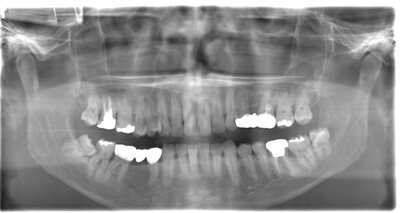

抜歯前

事前にCT撮影を行い神経との位置関係を確認して抜歯を行いました。右下親知らずは歯ぐきの中に完全に埋まり、

また斜めに生えていた為歯ぐきを切って親知らずの頭部分を分割して抜きました。

翌日多少の腫れが見られましたが痛みも痛み止めを飲めば過ごせる程度で出血はほとんどありませんでした。

基本情報

| 年齢・性別 | 24歳・女性 |

|---|---|

| 主訴 | 右下の親知らずが抜きたい |

| 治療内容 | 完全埋伏抜歯 |

| 治療期間 | 60分 |

| 治療費 | 約8,000円 |

| リスク・副作用 | 2〜3日は腫れと痛みがある。 必要に応じて抜歯を2回に分けて行う場合がある。 |